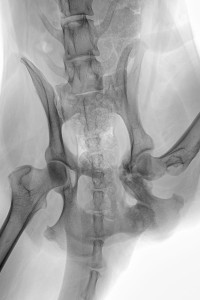

Die letzte RÖ-Kontrolle habe ich am 03. Feb. gemacht und da die Kallusbildung bis dahin weitestgehend abgeschlossen war und der Orthopäde uns grünes Licht gegeben hatte, habe ich Ihr Therapiegerät daher ausschleichend benutzt, d.h. etwa 3 Mal pro Woche für 15 Min.

Jenna läuft mittlerweile völlig beschwerdefrei, die linke Oberschenkelmuskulatur ist zwar nicht wieder komplett ausgebildet wie auf der rechten Seite, aber in der Laufbewegung sieht man fast keinen Unterschied mehr.

Und falls es in Zukunft zu einer schmerzhaften Arthrose im caudalen Bereich des Gelenkes kommen sollte, was wir alle nicht hoffen, werde ich das Therapiegerät wieder gern verwenden (bevor der Orthopäde zum Messer greift und den Femurkopf resezieren will).